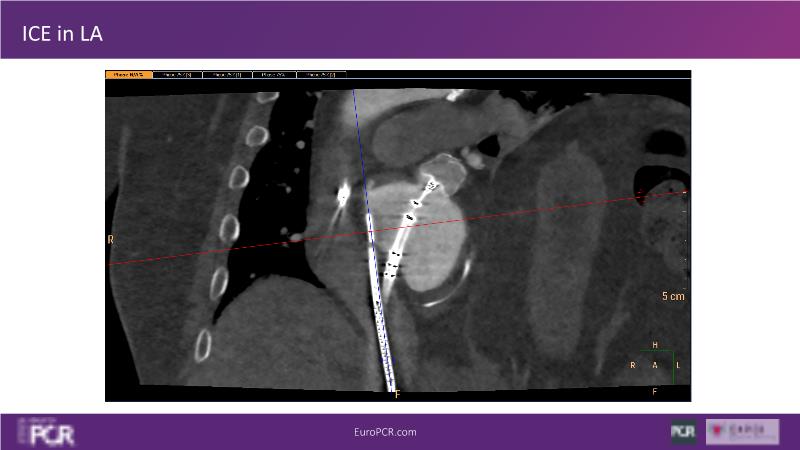

Explore this session to discover the latest innovations in interventional cardiology images, including the benefits of artificial intelligence and angio-CT in PCI/SHD procedures. Learn about Alphenix Evolve and the initial experiences with AI imaging in daily cathlab practice, alongside intraprocedural angio-CT guided LAAO, and engage in discussions on meaningful tools that can transform patient care.